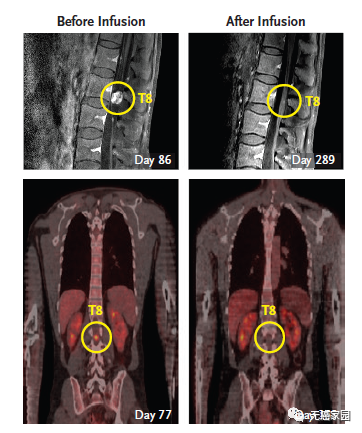

3次治疗之后,Grady脑中的所有肿瘤都发生了急剧的收缩。在第10次治疗后(3周后),Richard Grady拿到了他的脑部扫描结果,他脑部的5个肿瘤全部消除了!这真是个奇迹,就连医生都很惊喜,他所有的肿瘤都在消退。

第二轮CAR-T疗法结束后,Richard Grady脊索内肿瘤出现剧烈萎缩